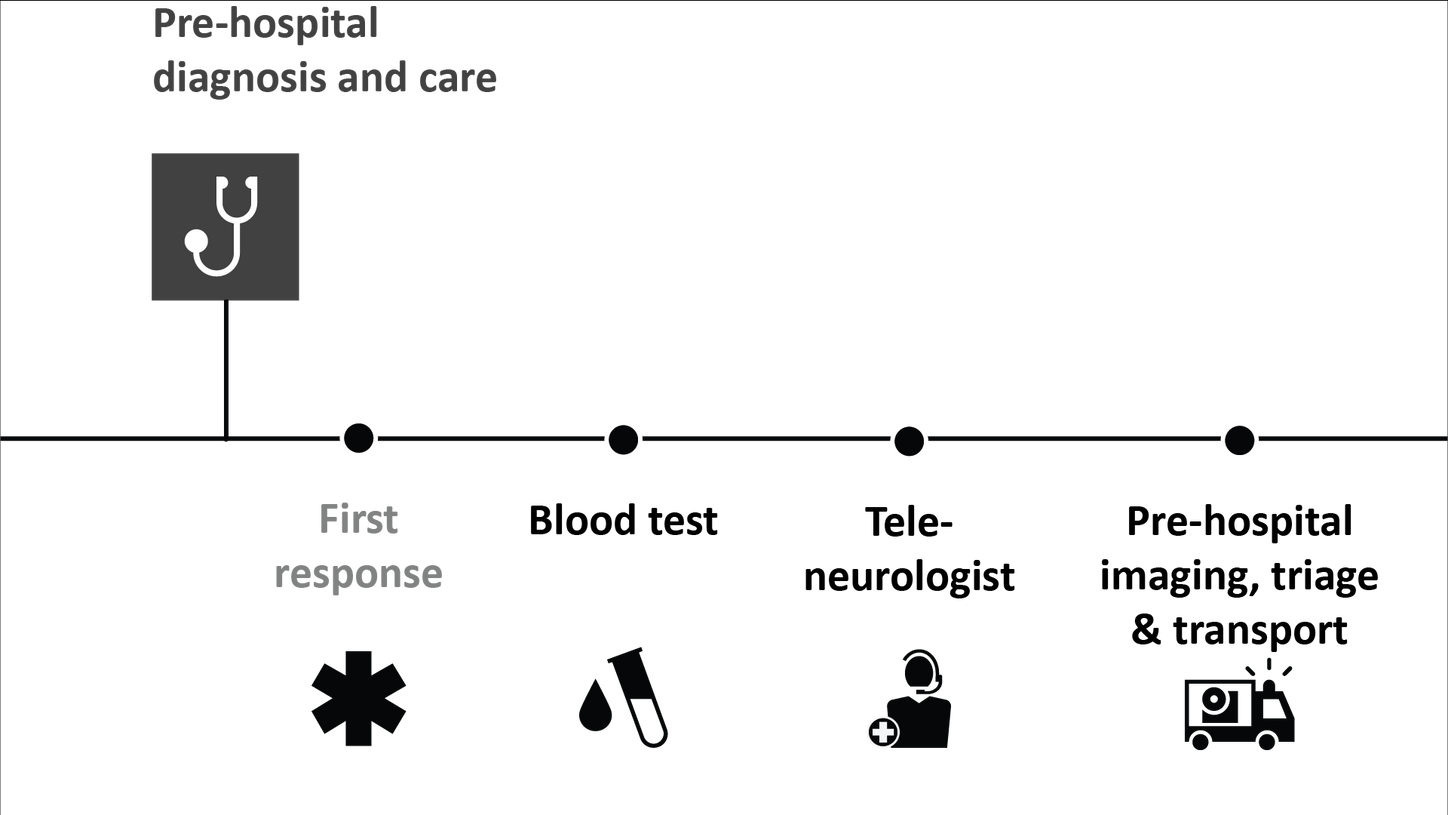

For stroke patients, time is of the essence. Every minute saved can positively impact patient outcomes.

That’s why it’s key to save time along the entire stroke pathway – from the onset of stroke to treatment and follow-up.

Stroke solutions

As your partner in stroke management, we keep you ahead of your time. Our advanced technologies let you speed up stroke care and transform care delivery along the entire pathway – from stroke screening and pre-hospital diagnosis and care to in-hospital diagnosis and treatment and (secondary) stroke prevention to follow-up imaging. Explore our offerings for stroke care!